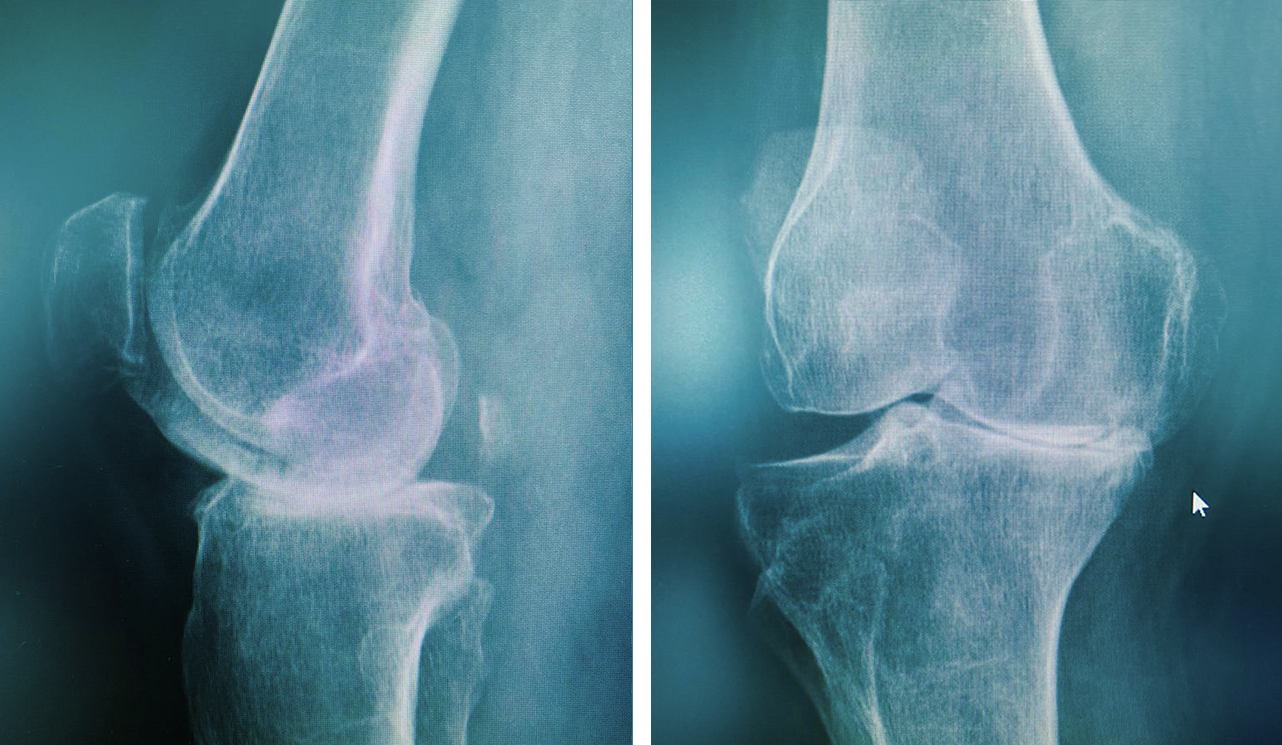

Artoz yani diz kireçlenmesi eklem kıkırdağının dejenerasyonuna eşlik eden kemik dokusunda bir artışla ortaya çıkan bir eklem hastalığıdır. Erkeklerden daha çok kadını etkiliyor. Osteoartrit, yaşlılarda ağrı ve özerklik kaybının en yaygın nedenlerinden biridir.

Kalça eklemi kireçlenmelerini temel olarak ikiye ayırabiliriz. Daha sık karşılaştığımız birinci grupta doğumsal yada sonradan oluşan yapısal bir bozukluk (kalça çıkığı, artrit, travma vb) nedeniyle zaman içinde kalça eklemindeki kıkırdakların aşınması sonucu ortaya çıkan kireçlenmeler yer alırken, ikinci grupta idiyopatik olarak adlandırdığımız sebebi belirlenemeyen kalça kireçlenmeleri yer alır.

Kalça eklemi kireçlenmesi, genelde 60 yaşından sonra görülse de özellikle doğumsal kalça çıkığı ve çocukluk çağında geçirilen kalça eklemi hastalıkları sonrasında çok erken yaşlarda da ortaya çıkabilir.